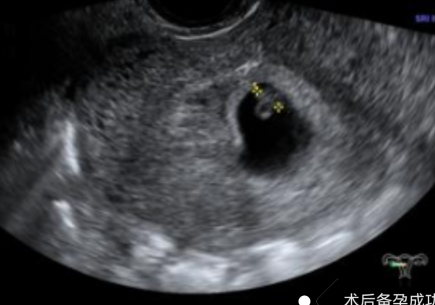

• 當驗孕棒上出現(xiàn)兩道紅杠新生命的驚喜與未知的忐忑是否同時涌上心頭?別擔心!紹興袍江醫(yī)院早孕門診以專業(yè)、溫暖、私密的服務(wù),為每一位準媽媽打造安心港灣,從孕早期開始,全程守護您與寶寶的健康。為什么選擇我們?1?精準檢測,科學(xué)診斷:配備先進檢測設(shè)備,提供血HCG檢測、超聲檢查等精準早孕篩查服務(wù),快速確認妊娠狀態(tài),排查宮外孕、胚胎發(fā)育異常等風(fēng)險,為孕期健康管理筑牢首道防線。?一站式孕早期管理:從孕期營養(yǎng)指導(dǎo)、科學(xué)補充葉酸,到孕期心理疏導(dǎo),再到定期產(chǎn)檢規(guī)劃,專業(yè)醫(yī)護團隊全程陪伴,為您解答